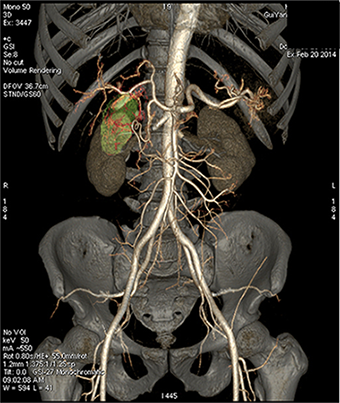

能谱 低keV图像血管成像

胆囊供血动脉   50keV

胆囊动脉及其分支发育细小,常规CTA难以完整显示,即使提高造影剂浓度、总量及注射流率也无法来满微小动脉显示的需求,受扫描时相影响较大。

GSI扫描能使用低keV 图像满足空间分辨率和密度分辨率兼顾的要求,在常规造影剂注射方案情况下,一次扫描通过调整keV同时满足诊断及微小动脉显示需要。该方法可在临床解剖研究、病变血供发现、血管受侵状况、手术指导等方面有重要作用。